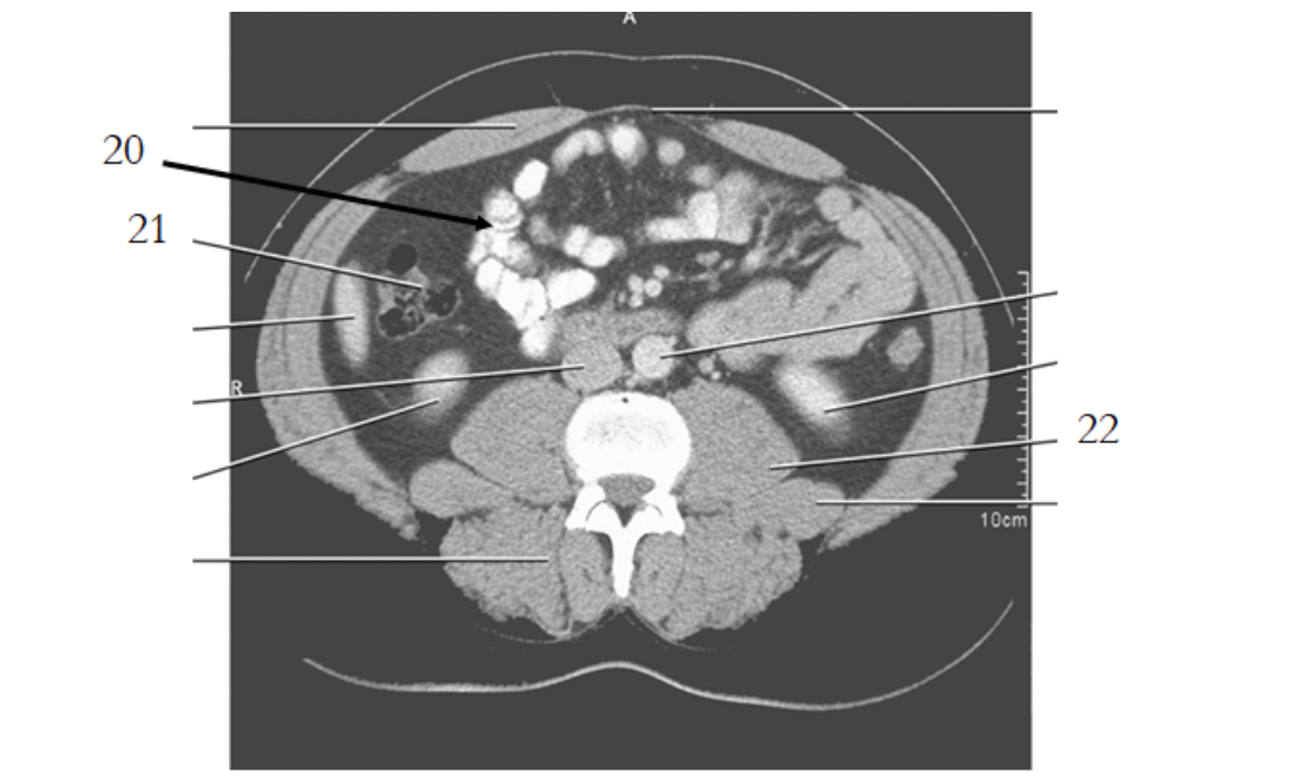

20

aorta

small bowel

21

large bowel